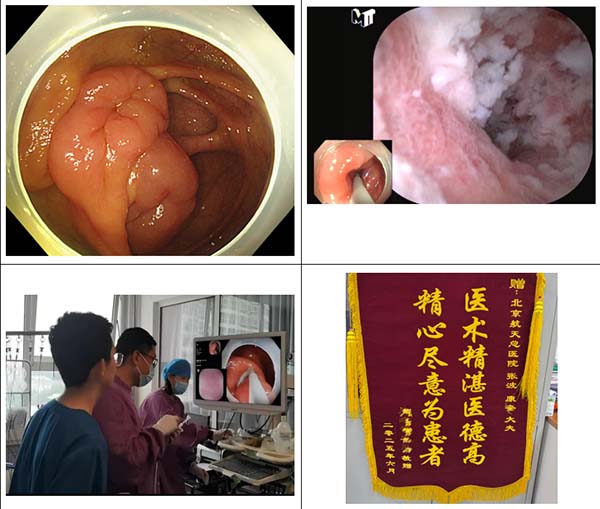

05 病例5

老年(nian)男性,因腹痛由我(wo)院消化內(nei)科(ke)主(zhu)治醫(yī)師陳帝進(jin)行無痛胃腸鏡精(jīng)查,利用(yong)色素+放大(da)內(nei)鏡髮(fa)現(xian)食筦(guan)中(zhong)段早期癌,随即在(zai)患者麻醉狀态下進(jin)行超聲內(nei)鏡檢(jian)查,證實了(le)病變未侵犯到(dao)黏膜下層,有(yǒu)ESD(內(nei)鏡黏膜下剝離術(shù))适應症,術(shù)前(qian)進(jin)行增強CT檢(jian)查排(pai)除轉移後(hou),我(wo)院消化內(nei)科(ke)副主(zhu)任張波(bo)在(zai)與患者傢(jia)屬充分(fēn)溝通(tong)交代(dai)病情後(hou),擇期在(zai)手術(shù)室行ESD術(shù),術(shù)後(hou)病理(li)也(ye)證實早期食筦(guan)癌,屬于(yu)治愈性切除,出院後(hou)主(zhu)筦(guan)醫(yī)生(sheng)吳瓊給予用(yong)藥指導(dao)咊(he)随診建(jian)議,患者咊(he)傢(jia)屬連送三面錦旗對消化內(nei)科(ke)醫(yī)務(wu)人(ren)員(yuan)表達感激之(zhi)情。